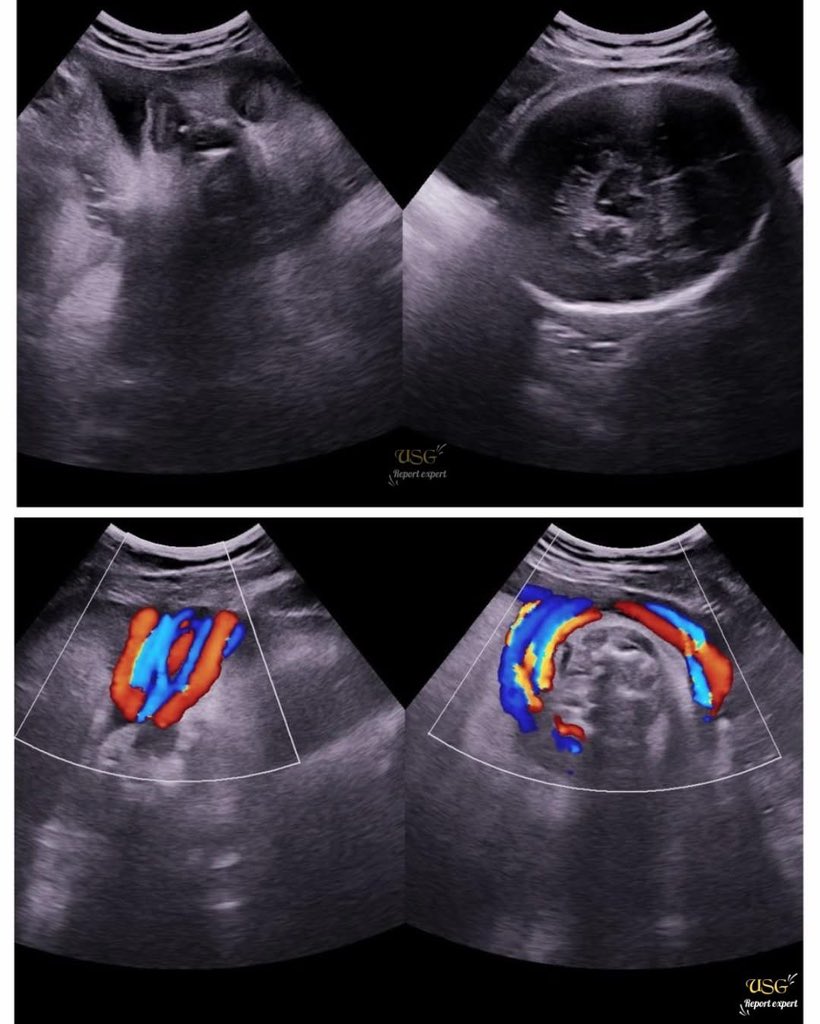

Comment on this lesion !! Diagnose 😱😱😱

#medico #ultrasoundeducation #ultrasounds #usg #ultrasoundtechnologist #cysts